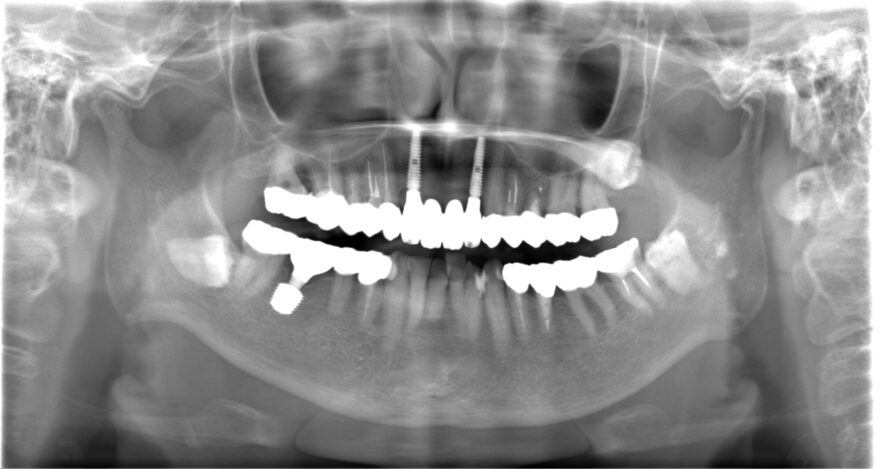

初診時のレントゲン写真

合計3本のインプラントが入りました。